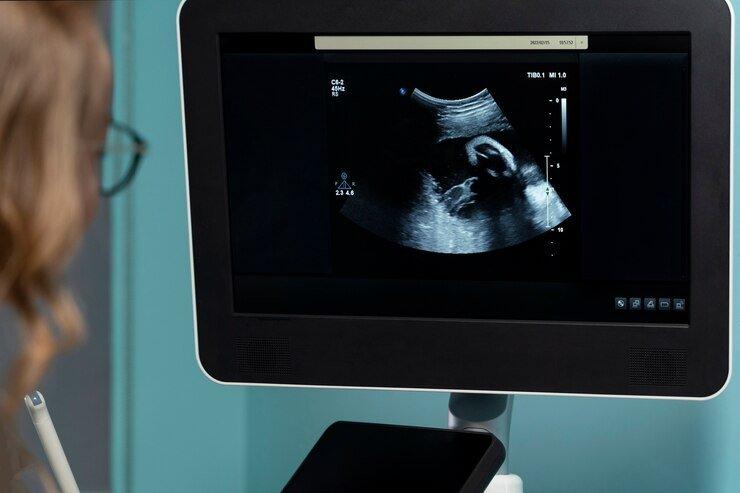

TRIBUNHEALTH.COM - Inseminasi Intrauterin (IUI) bisa menjadi salah satu opsi yang bisa dilakukan untuk pasangan yang masih menantikan kehadiran buah hati.

Ini merupakan bentuk teknik reproduksi berbantu yang patut untuk dicoba, sebelum bayi tabung.